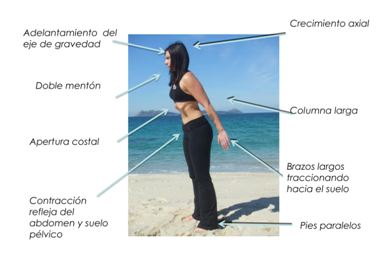

Los ejercicios se realizan adoptando diferentes posiciones en base a unas

determinadas pautas de ejecución que facilitan y acentúan el efecto

Hipopresivo caracterizado por: adelantamiento del eje de gravedad,

autoelongación axial, decoaptación de la articulación de los hombros,

apertura costal y apnea espiratoria.

Figura

3. Pautas técnicas de ejercicio HD (Rial y Villanueva, 2011)